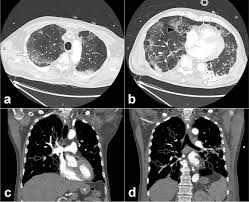

In fact, symptoms may be so vague and fleeting that people just brush them. Possible signs of a stroke in cats include: Ct scanning is fast, painless, noninvasive and accurate. Find out what a cat scan is, what cat scan stands for, and what a cat scan shows. If your symptoms or other findings suggest that the cancer could be more advanced, however, you may need to have ct scans of the head, chest, and/or abdomen.

Cat illnesses can be broken down into several categories: If contrast leaked under the skin, the patient should look for increased redness. Strokes in cats can be either ischemic (the blood supply is cut off) or hemorrhagic (blood is leaked out into the brain). If your symptoms or other findings suggest that the cancer could be more advanced, however, you may need to have ct scans of the head, chest, and/or abdomen. Possible signs of a stroke in cats include: Investigations most studies that classify strokes into sub categories are likely to use brain imaging. Stroke series video 3 of 7: Ct scanning is fast, painless, noninvasive and accurate. We'll explain why your doctor may order an abdominal ct scan, how to prepare for the procedure. Computed tomography, more commonly known as a ct or cat scan, is a diagnostic medical imaging test. By knowing the signs and symptoms of stroke, you can take quick action and perhaps save a life—maybe even your own. Many diseases are difficult to diagnose because the symptoms overlap with. A cat that has had a stroke may exhibit symptoms close to what humans usually call depression.

Learn how this test works, as well as its benefits and risks. Whatever type of stroke a cat has, the symptoms that develop are determined by how much brain tissue is affected, how severely it is affected, and where in the brain it is located. Types, symptoms, causes, how to diagnose them. If your symptoms or other findings suggest that the cancer could be more advanced, however, you may need to have ct scans of the head, chest, and/or abdomen. Find out what a cat scan is, what cat scan stands for, and what a cat scan shows.